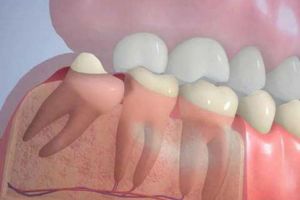

Yirmi yaş dişleri olarakta bilinen üçüncü azı dişleri sıklıkla kemik içerisinde gömülü kalabilir ya da yanlış bir pozisyonda sürebilir. Bu durumda cerrahi yöntemlerle lokal anestezi altında çekilmeleri gerekmektedir. Bazen gömülü kalmış köpek dişlerine de aynı tip cerrahi işlemler uygulanabilir.